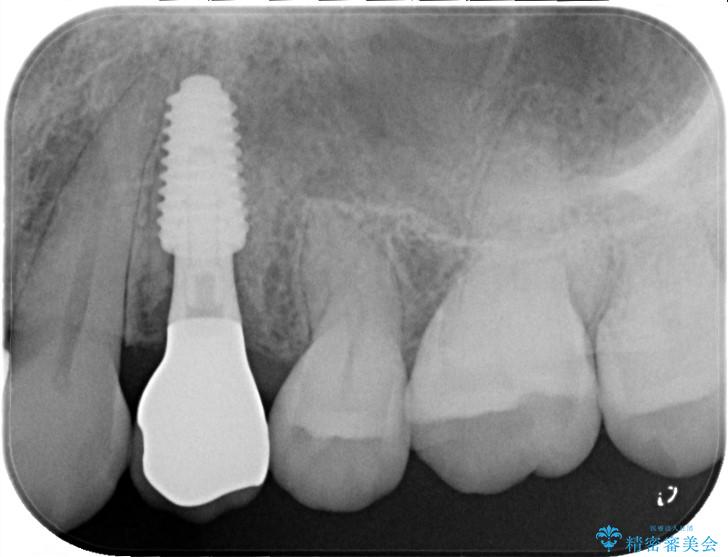

検査の結果、左下4番の歯周ポケットが非常に深くなっていました。これは、歯の根が割れている「歯根破折」の典型的なサインです。

患者様には、根の部分が割れている可能性を説明し、被せ物を外して内部を直接確認することとしました。

根が真っ二つに割れている「垂直性歯根破折」の場合、残念ながら歯を残すことが難しく、放置すると周囲の骨まで溶かしてしまいます。そのため、抜歯後の噛み合わせを回復する方法として、隣の歯を削らずに独立して噛めるインプラント治療をご提案しました。

被せ物を除去し、マイクロスコープにて内部を強拡大で確認したところ、歯の根の深い位置まで真っ直ぐにひびが入っていることを確認し、保存が不可能な状態であったため抜歯をすることとなりました。